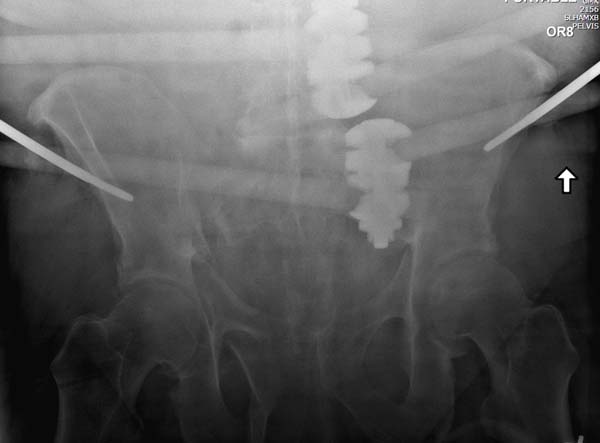

Двухстороннее повреждение крестца и травматическая ампутация бедра, где

неопытной бригадой дежурантов установлен верхний наружный фиксатор для

стабилизации. На третий день ревизия на более стабильный, и

окончательная фиксация. Первые снимки после стабилизации таза, и другие,

где показаны (параллельные) правильная установка на AIIS т.е на месте

прикрепления прямой мышцы бедра. Ампутация закончена костно пластическим

методом.